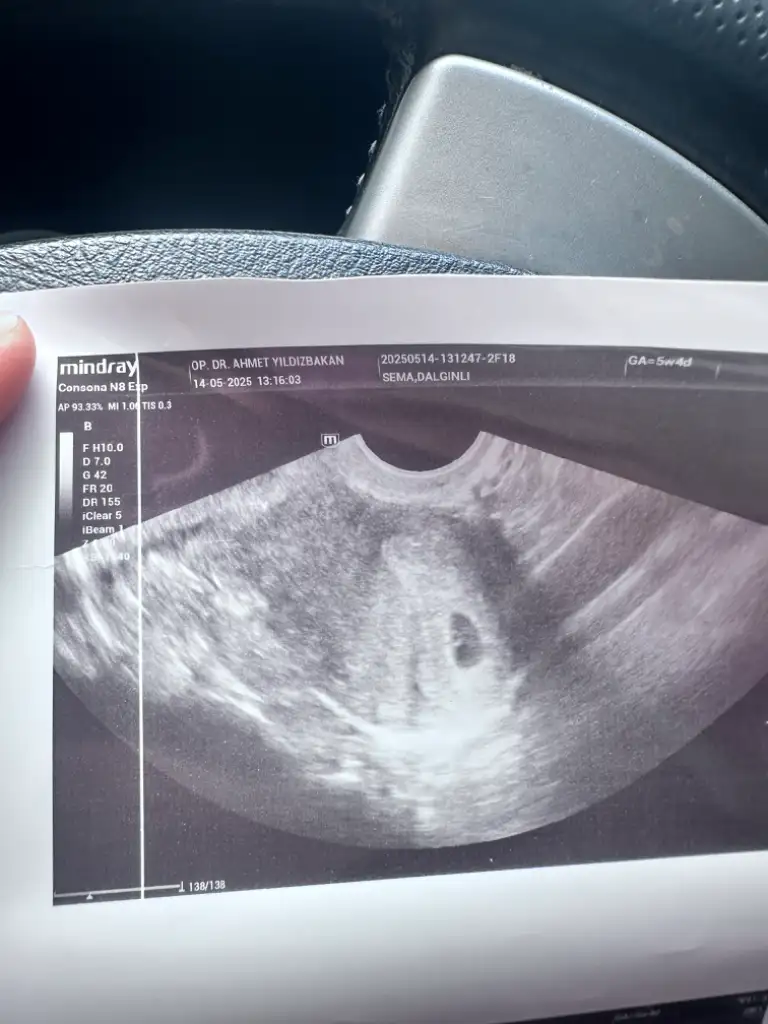

Çok sevindim canımKızlar bu sabah ilk randevum vardı, kese ve yolk kesesi göründü10 gün sonra kalp atışını duyarız dedi. Üstümden bir dağ kalktı resmen kaç gündür tam olarak hamileliğime inanamadım… günler boyu kese görünür mü, dış gebelik mi, boş gebelik mi diye türlü senaryolar düşündüm ama bugün o hayırlı haberi aldım Rabbime bin şükürler olsun Allah isteyen herkese bu mutluluğu yaşatsın inşallahhh

Bu arada en sinir olduğum nokta doktora gebelik haftasını sormamamunuttum… doktorda söylemedi, ultrason kağıdında da yazmıyor. Bi ara doktor kese için 11 mm falan dedi … Uygulamaya bakarsak bugün 5+6 haftalık